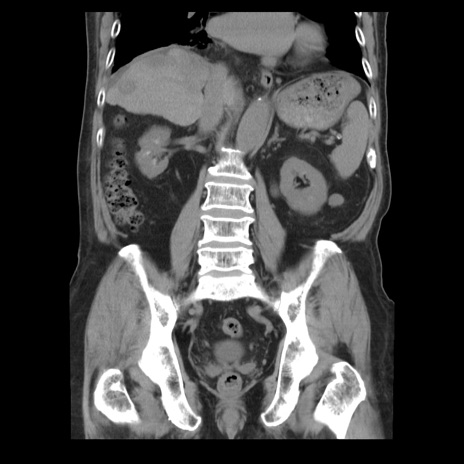

症例21(冠状断像)

【症例】70歳代男性

【主訴】腹痛

【現病歴】肝硬変・肝細胞癌にてかかりつけの方。約9時間前に食後より腹痛出現。症状が徐々に増悪し、嘔吐出現したため来院。

【既往歴】肝硬変、肝細胞癌(RFA、TACE後)

【身体所見】意識清明、表情苦悶様、BT 36℃、BP 129/78mmHg、P 88bpm、SpO2 97%(RA)、右上腹部から心窩部にかけて圧痛あり、反跳痛なし、筋性防御あり。

【データ】WBC 5800、CRP 0.16